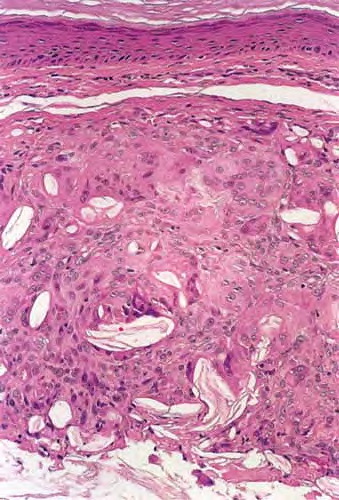

Keratin granuloma = حبيبوم الكيراتين